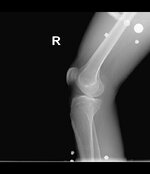

Patella kondromalezi : Sol diz grade 1, sağ diz grade2/3 .

bugün baltalimanındaki spor hekimine gittim canan hanım mr ve röntgen istedi, röntgeni çektirdim mr ıda çektircem sonra gidicem bakalım ama dizler pek güzel durmuyor :)

diz1.jpg diz2.jpg diz3.jpg